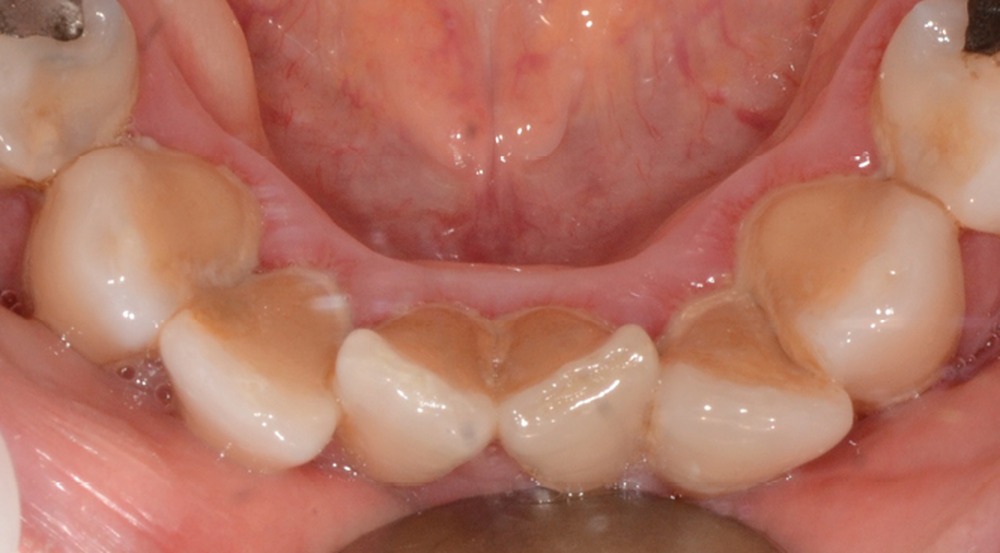

C’est à ces questions que nous permettront de répondre les deux premiers conférenciers, parodontologistes : le Dr Béatrice Straub nous présentera le renfort parodontal minéralisé, technique qu’elle a développée et pratique depuis de nombreuses années, pour éviter les préjudices des mouvements orthodontiques à risque, notamment lors des décompensations préchirurgicales (fig. 1a-d) ; le Pr Anton Sculean abordera le thème des greffes, avec leurs indications, les différentes techniques à privilégier et illustrera ses propos par de nombreux cas cliniques aux résultats esthétiques impressionnants.